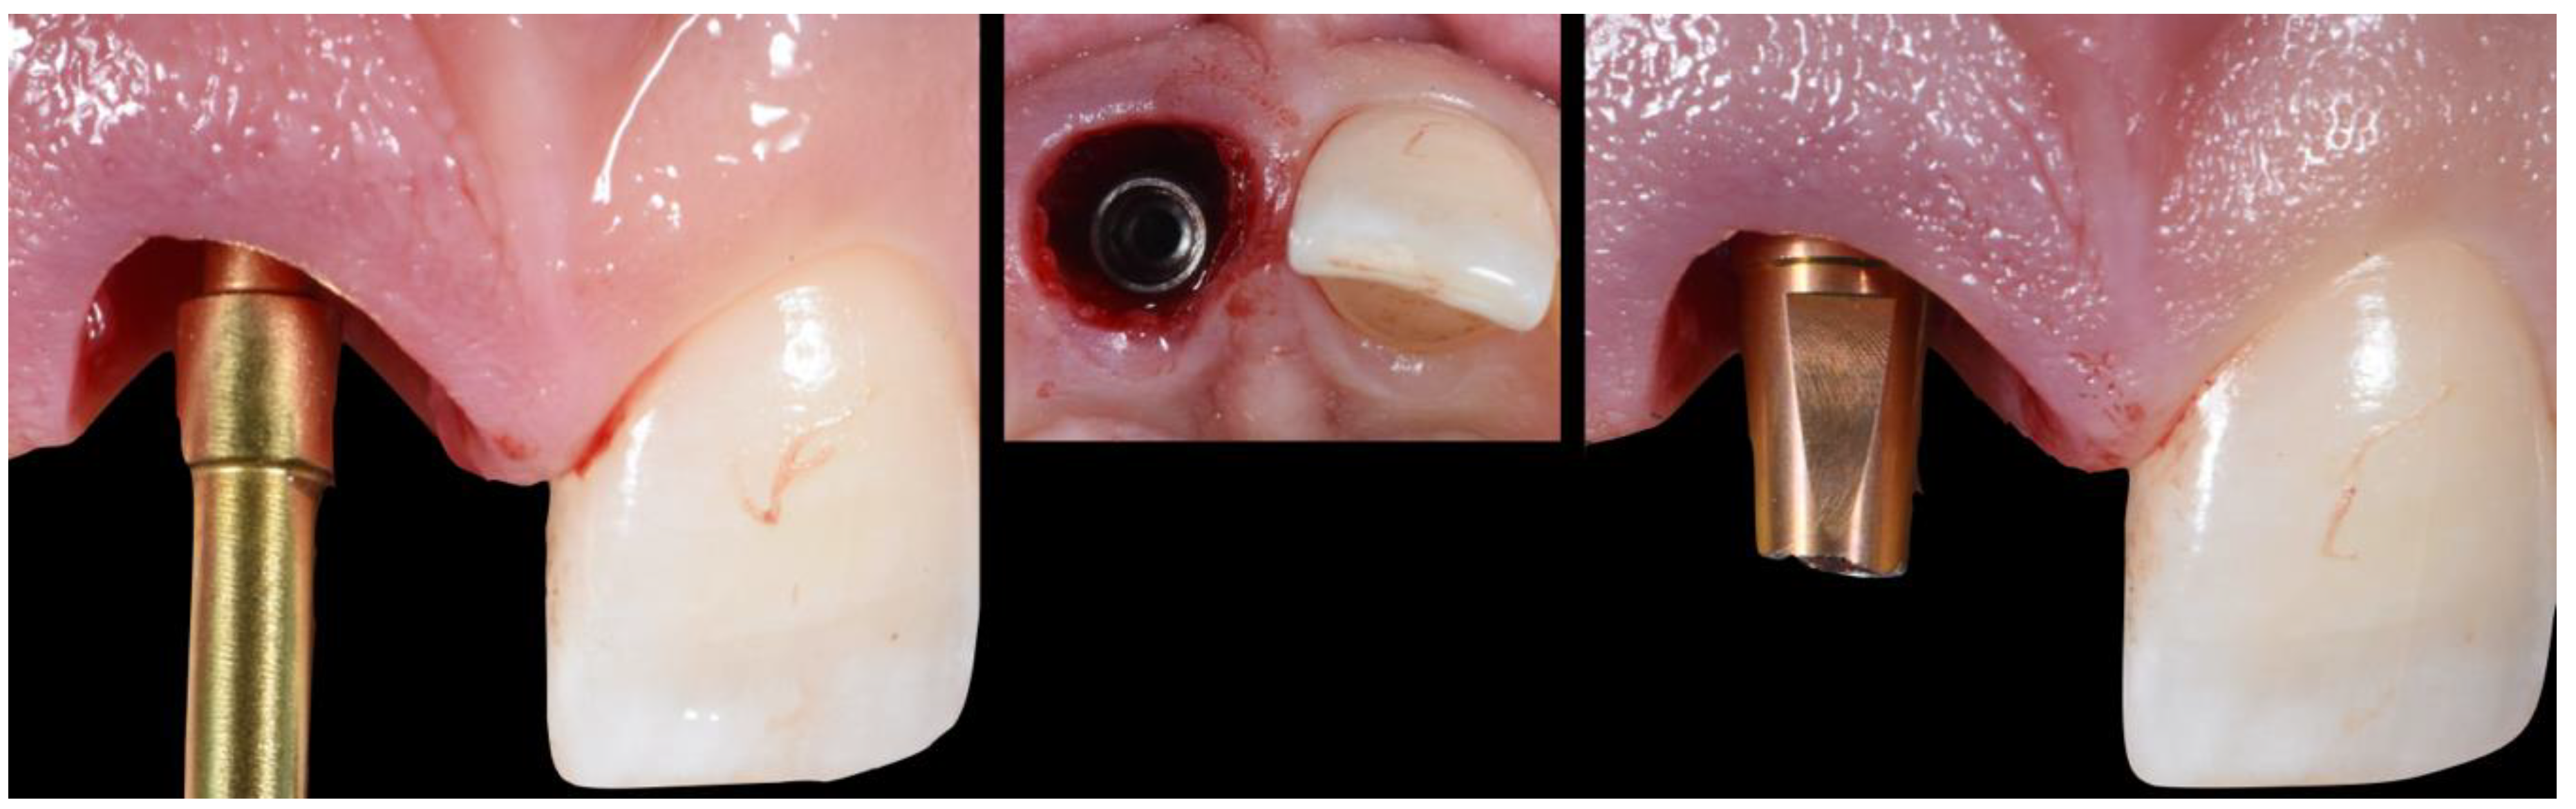

- (A)

- Extraction socket presentation, where the red line represents the supra-periosteal pouch flap.

- (B)

- Three-dimensional implant positioning, where different locations of the implant axis can achieve the desired location of the platform and neck of the implant.

- (C)

- Fits abutment selection, where the shoulder is located 0.5 mm apically to the cervical gingival margin.

- (D)

- Membrane adaptation, being in contact with the internal wall of the socket.